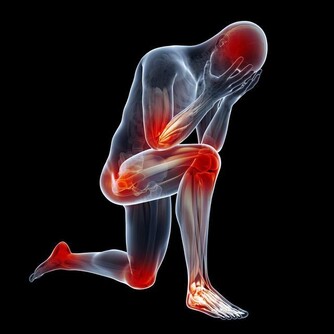

鼻咽癌晚期,殘酷的五個字,竟然和一名15歲少年聯系在了一起。由於發現晚,孩子也許只剩下5年時間…… 小明(化名)性格溫順,言語不多。父母在浙江打工,他跟著爺爺奶奶在老家安徽生活。3個月前,一直忙於農活的爺爺奶奶才注意到,孩子的脖子有些異常。 「脖子上就長了個包,有點硬,但是他身體都好好的, 我們也不知道呀。」現在回想起來,老人非常懊悔。由於缺乏醫學常識,小明脖子上的「包」越長越大,足足在脖子上突出了一個小拳頭大小,才告訴了父母。在當地醫院的檢查中,並沒有找到病因,後來父母把孩子接到杭州第一人民醫院,活檢證實是鼻咽癌。 「他這個年紀,怎麼會得癌症?」誰都不相信,尤其是小明的媽媽。 鼻咽癌在成人當中比較常見,兒童非常少見,但現在20、30歲的鼻咽癌患者在逐步增加,為什麼小明卻感染了呢? 影響因素一: 鼻咽癌的發病是多方面的原因,和EB病毒有關系,95%以上的成人都攜帶了這種病毒,它是傳染性單核細胞增多症的病原體,所以家長不要嘴對嘴的給孩子餵食物。 影響因素二: 鼻咽癌和生活習慣、外部環境都脫不了干係。喜歡吃醃漬的食物,比如鹹魚、臘腸、泡菜等,容易患上這種癌症。 【醃漬食品三大罪狀】 1.含有致癌物質——亞硝酸胺 醃漬食品在醃制過程中會產生亞硝胺前體物亞硝酸鹽。人的胃液pH值在1~3時,亞硝酸或硝酸鹽(需經細胞還原成亞硝酸鹽)可與細胞中的仲胺合成亞硝胺類化合物。這些物質有較強的致癌作用。 2.容易造成人體維生素C缺乏和結石 蔬菜在醃制過程中,維生素C被大量破壞。醃制後,維生素C的成分幾乎「全軍覆滅」。大量吃醃菜,人體維生素C缺乏。因此,適當吃點醃菜可以調節胃口,增加食慾,但若嗜食醃菜成癖,則是不可取的。如果長期食用,容易引起各種疾病。 另外,醃制的酸菜中含有較多的草酸和鈣,由於它酸度高,食用後不易在腸道內形成草酸鈣被排出體外,而會被大量吸收,草酸鈣就會結晶沉積在泌尿系統形成結石。 3.影響黏膜系統,對腸胃腎髒有害 由於食品在醃制過程中,需要大量放鹽,這會導致此類食物鈉鹽含量超標,造成常常進食醃制類食品者腎髒的負擔加重,發生高血壓的風險增高。 此外,高濃度的鹽分還會嚴重損害胃腸道黏膜,故常進食醃制類食品者,胃腸炎症和潰瘍的發病率較高。 如果一定要吃,也要在醃制15天後亞硝酸鹽下降至安全的劑量範圍內食用。 鼻咽癌早期有高達80%的治癒率,但是由於小明的情況比較特殊,家長反應慢,所以拖的時間較長,癌細胞已經轉移。「情況並不是特別樂觀。」李勇也表示惋惜,「治好了,可能也就5年時間吧。」 鼻咽癌的早期症狀 涕中帶血:早晨起床時,經常流鼻血,或是鼻涕呈淡粉色,有時帶血絲。 耳鳴,聽力減退,耳內閉塞感。頭痛:單側頑固性頭痛,偏頭痛多發生在顳頂部。頸部淋巴結腫大。鼻塞。 因為早期症狀不典型,多數被誤診為鼻炎,中耳炎,頸部淋巴結結核等。所以大家需要注意了,尤其是家長,如果一發現這些症狀,一定要及時就醫! 首頁還有更多熱門文章喔 網址傳送門 ww.happies.news